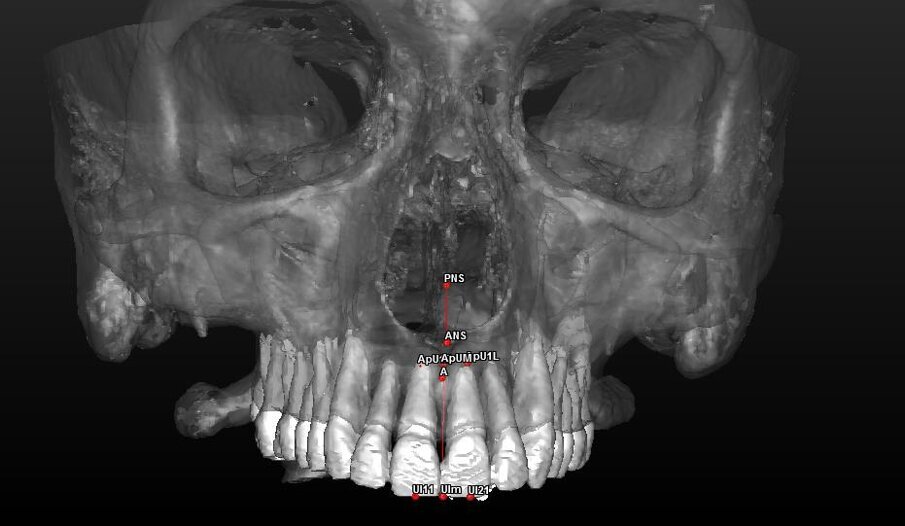

- 7 landmark per la valutazione scheletrica (Tab. 1) (Figg. 2, 3).

| U11 |

Punto medio del margine incisale dell’incisivo centrale di destra. |

| U21 |

Punto medio del margine incisale dell’incisivo centrale di sinistra. |

UIm: Punto mediano dei margini degli incisivi U11 e U21;Dai landmark dentali (U11, U21, ApU1R e ApU1L) sono stati ricavati due punti mediani calcolati direttamente dal software:

- ApUM: Punto mediano degli apici degli incisivi ApU1R e ApU1L.

Con questi è stato possibile tracciare una retta che passasse tra i punti UIm e ApUM e che possa essere considerato così il vero asse mediano degli incisivi centrali definendolo “Asse Incisale Superiore”.

Dai landmark ossei ANS e PNS è stata tracciata una retta passante per questi due punti definita “Asse Spinale”.

Componente dentale (Tab. 4) (Figg. 8, 9):

Fig. 8_Valutazione della componente dentale in visione para-frontale.